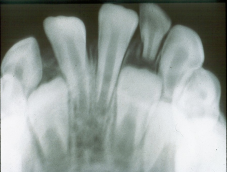

What size of receptor for occlusal radiographs is used for adults? Children?

Adults: size 4

Children: size 2

What are the clinical indications for a Maxillary Anterior Occlusal (Adults) radiograph?

What are the indications for a Maxillary Standard Occlusal radiograph?

Detecting the presence of unerupted canines, supernumeraries.

Evaluation of the size and extent of lesions.E.g cysts, tumours

Evaluating fractures